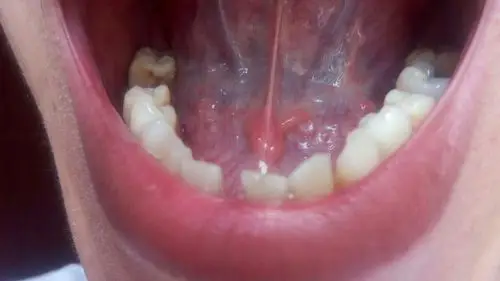

口腔舌头下面长了好多的小水泡